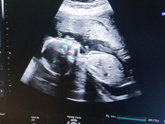

Девочки, сос. На какой неделе точно узнали пол? Есть кто на 12? Мы хотим делать гендер пати, и я всем говорю, что на 12 неделе узнаем и сделаем, но меня настраивают не делать так рано, типа вдруг не точно будет. Вот не знаю

Много от кого слышала "я чувствую, что у меня будет мальчик/девочка" (нужное подчеркнуть). Не понимала, пока сама не забеременела. Теперь хоть убей, чувствую, что будет девочка (это не связано никак с "хочу", ибо мне вообще не принципиально кто будет, … Читать далее